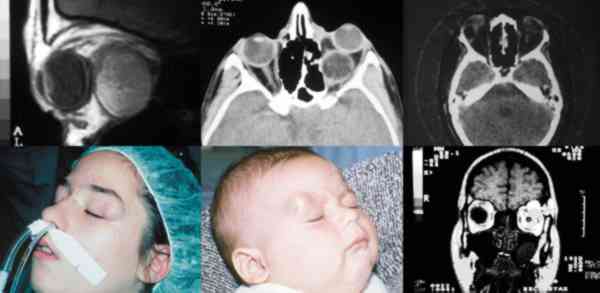

Figura 8. Las técnicas neurorradiológicas son fundamentales en la

cirugía de la órbita.